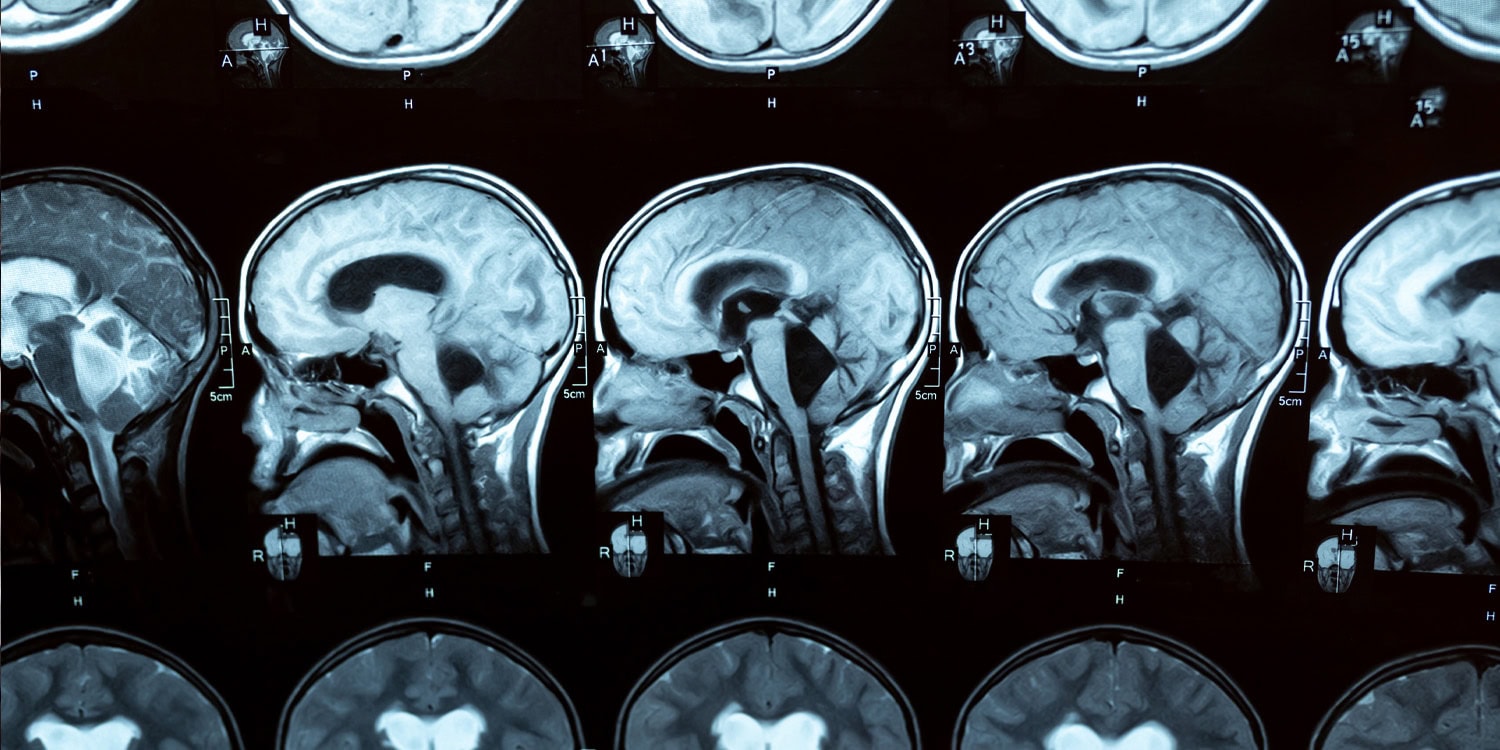

Болезнь Альцгеймера — это тот ещё коварный вор: приходит незаметно, подкрадывается к памяти, мышлению и поведению, перечёркивая всё, что делало нас «нами». В 70% случаев, когда говорят о деменции, подразумевают именно Альцгеймера. Причина — скопление в мозге белковых залежей: бета-амилоид превращается в бляшки, тау-белок — в клубки. Они настолько мешают общению между нервными клетками, что даже самый упёртый мозг рано или поздно сдаётся на милость судьбы.

Но подвох в том, что мозг начинает портиться задолго до того, как первые признаки проберутся наружу. Учёные под руководством Диего-Мартина Ломбардо решили поискать очень ранний маркер Альцгеймера — и заподозрили в этом одну странную «ссору» между двумя главными сетями мозга.